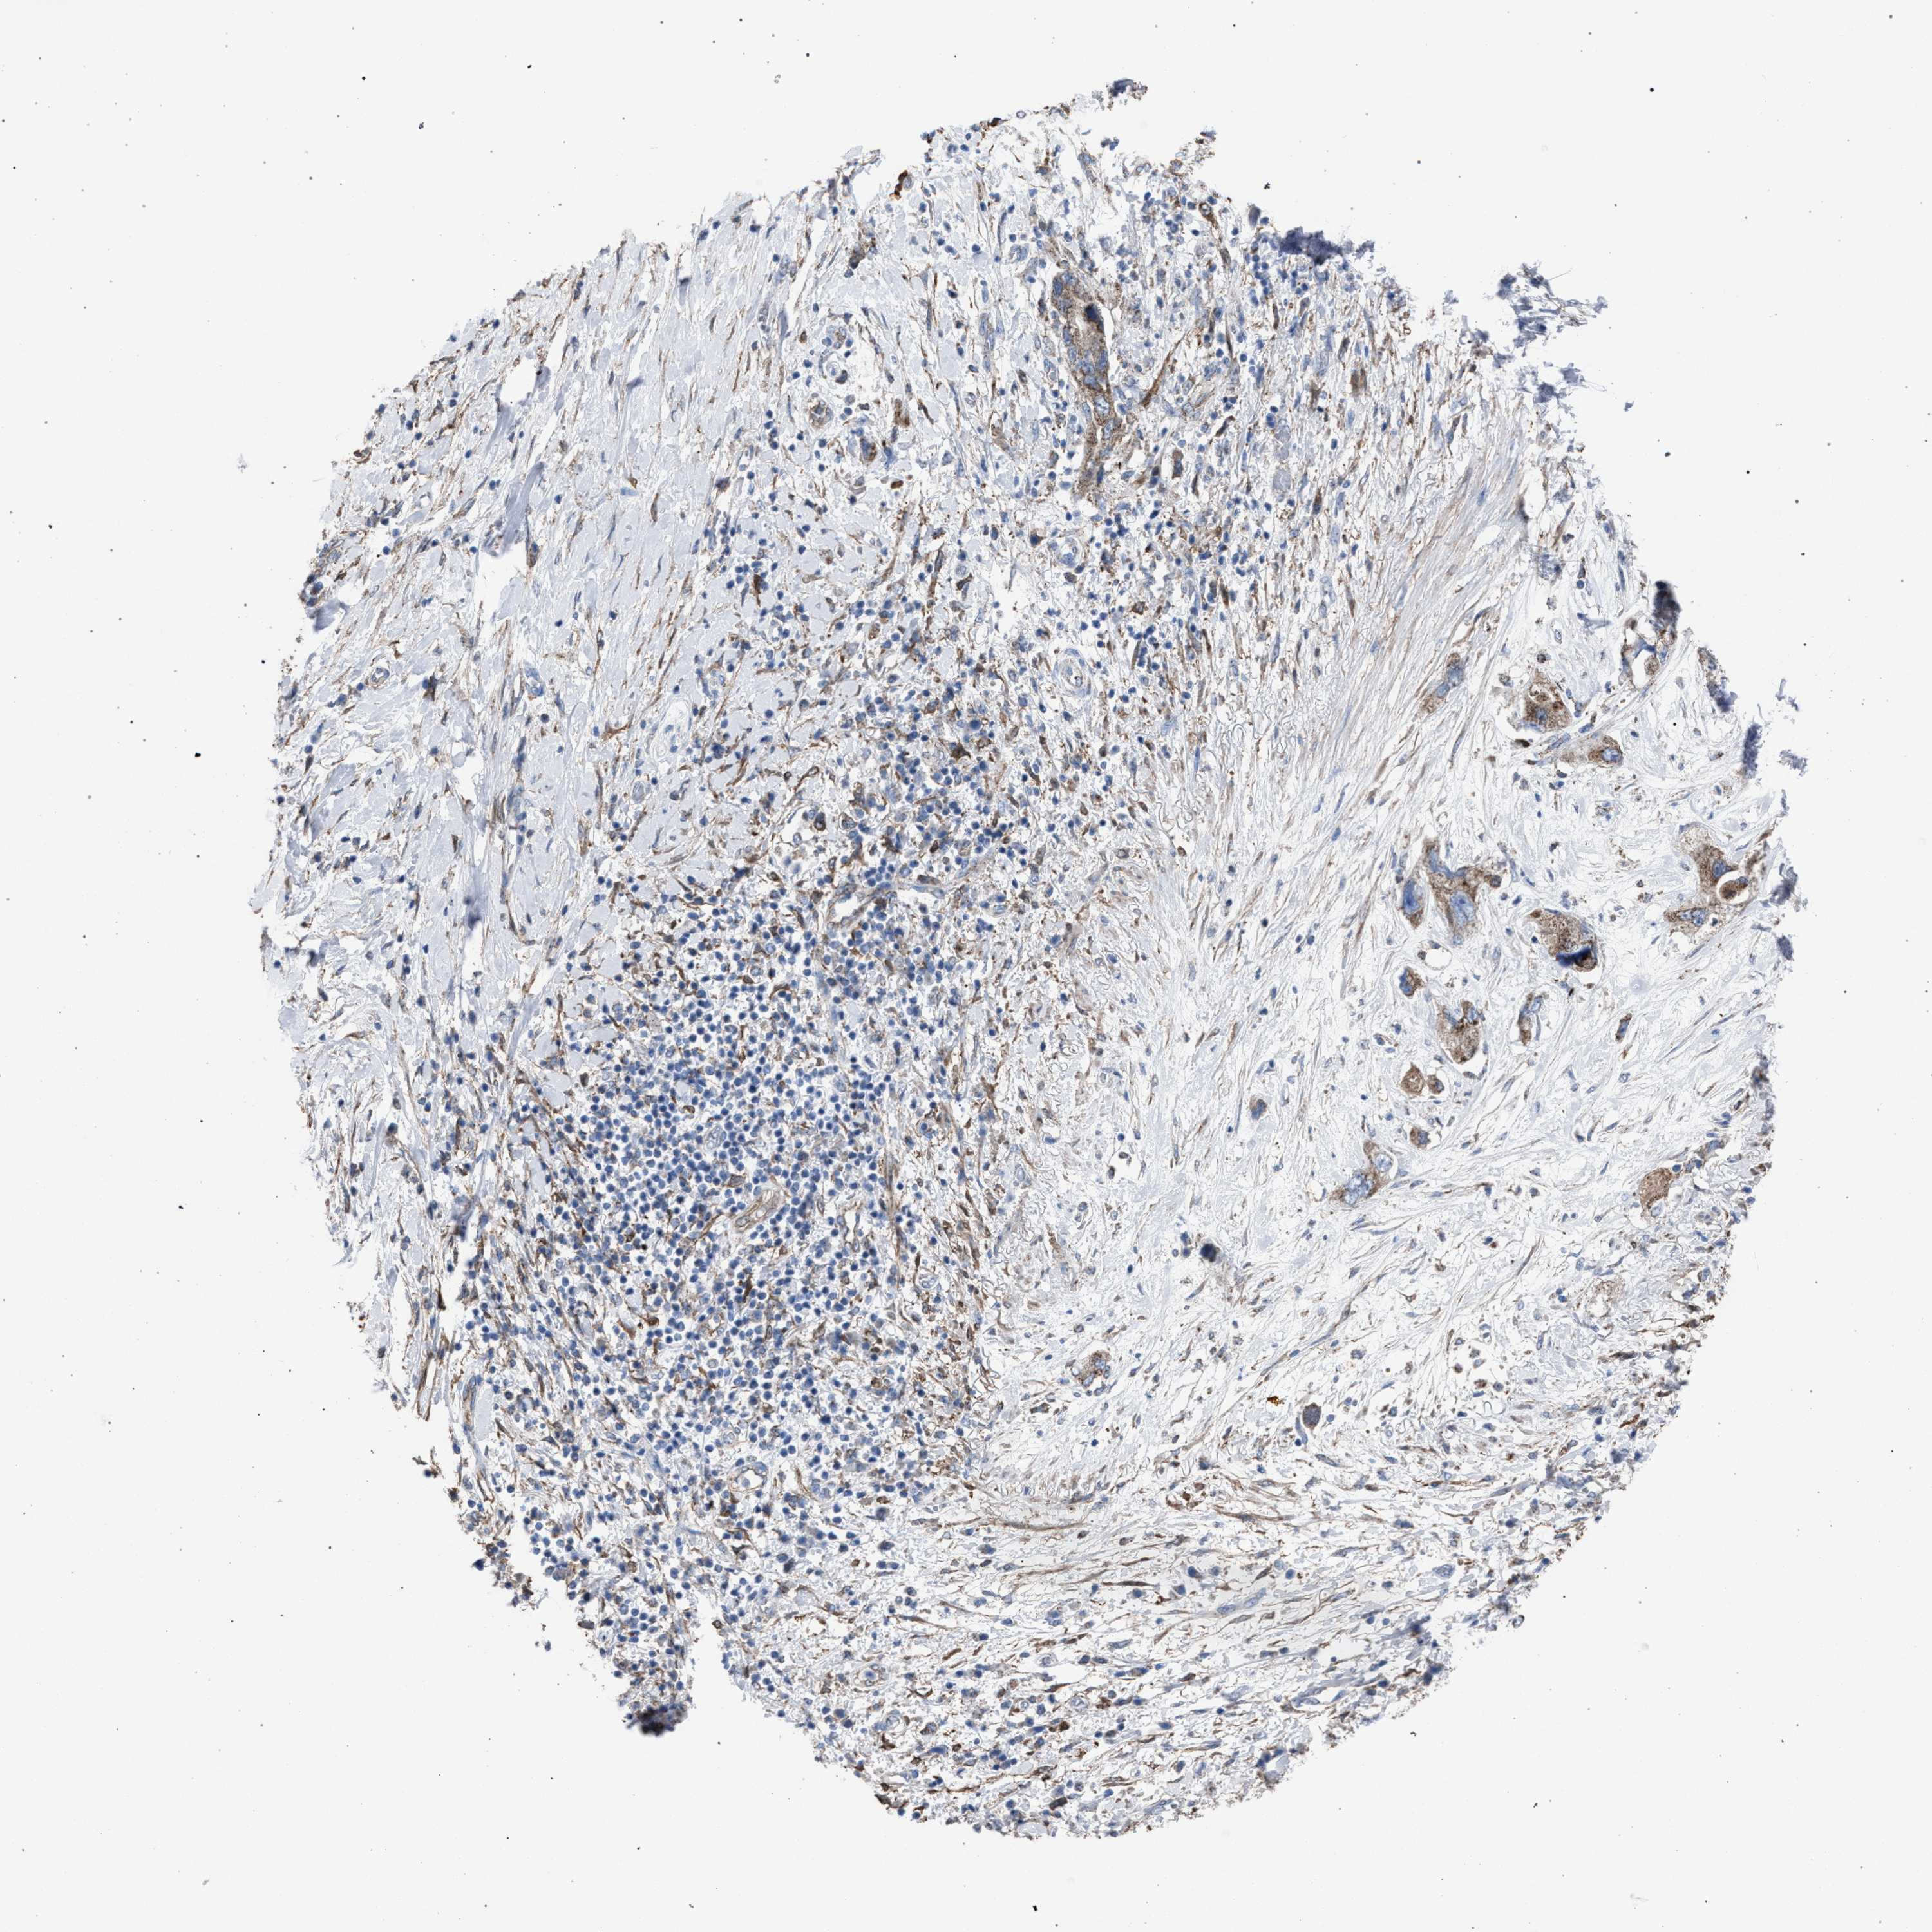

PANCREATIC CANCER - Protein expressioni

A mouse-over function shows sample information and annotation data. Click on an image to view it in a full screen mode. Samples can be filtered based on level of antibody staining by selecting one or several of the following categories: high, medium, low and not detected. The assay and annotation is described here.

Note that samples used for immunohistochemistry by the Human Protein Atlas do not correspond to samples in the TCGA dataset.

Antibody stainingi

Antibody staining in the annotated cell types in the current human tissue is reported as not detected, low, medium, or high, based on conventional immunohistochemistry profiling in selected tissues. This score is based on the combination of the staining intensity and fraction of stained cells.

Each image is clickable and will lead to virtual microscopy that enables deeper exploration of all samples and also displays staining intensity scores, fraction scores and subcellular localization as well as patient and tissue information for each sample.

Antibody HPA021302

Antibody HPA021311

Antibody HPA021479

Adenocarcinoma, NOS